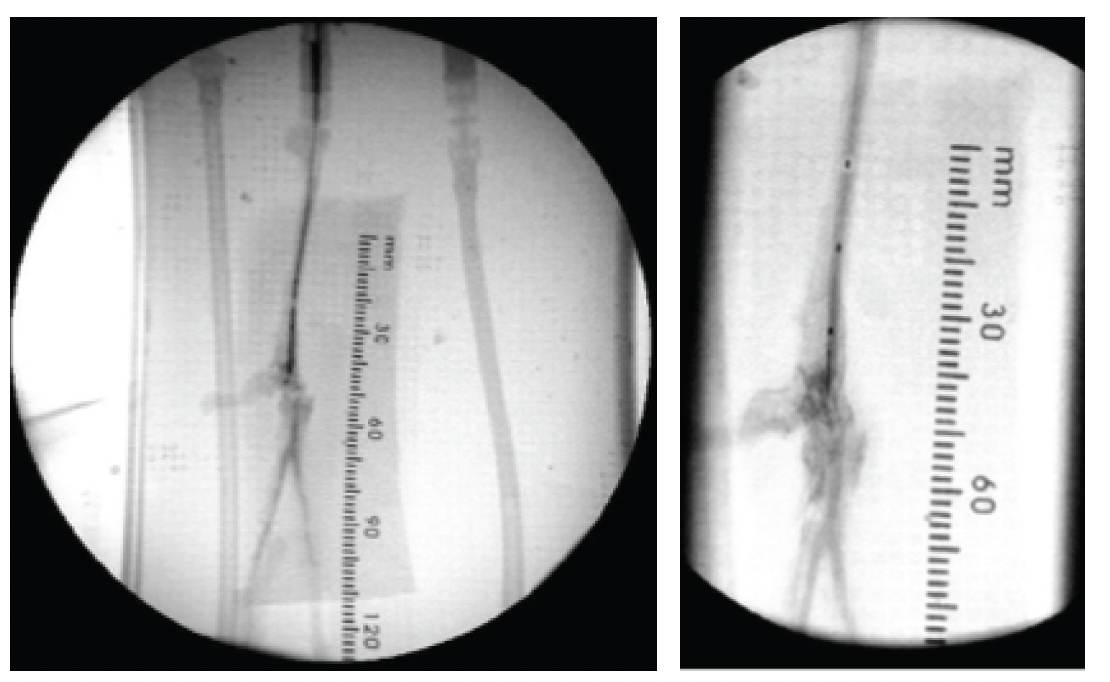

The access site used for the procedure simulated a contralateral approach from the right femoral artery. A guiding catheter was brought through the access site over to the left femoral artery up to the connection point between the vascular model and the connected popliteal artery. Under fluoroscopy and using contrast injection, an attempt to cross the occlusion was

performed without success using a V-18 ControlWire guidewire (Boston Scientific) over an 0.018˝ Rubicon 18 support catheter (Boston Scientific) (Figure 3A). A second unsuccessful attempt was made with the SoundBite Crossing System without activation (no shockwave transmitted; Figure 3B).

Recanalization was then attempted using the activated SoundBite Crossing System, resulting in recanalization of both the occluded posterior tibial and peroneal arteries (total procedure time, 4 min) (Figures 3C and 3D).